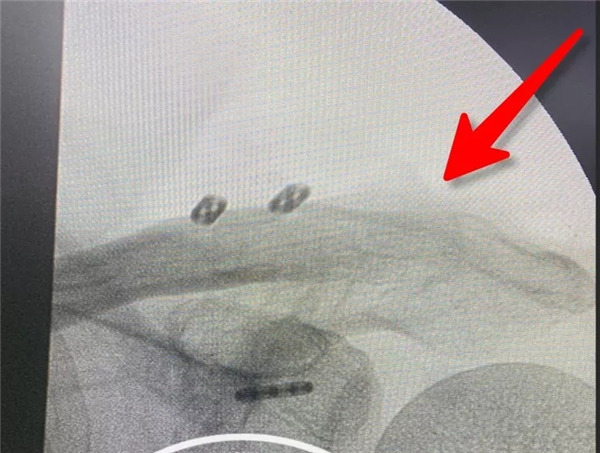

術(shù)前拍片--患者的肩鎖關(guān)節(jié)脫位屬于Rockwood  5型脫位